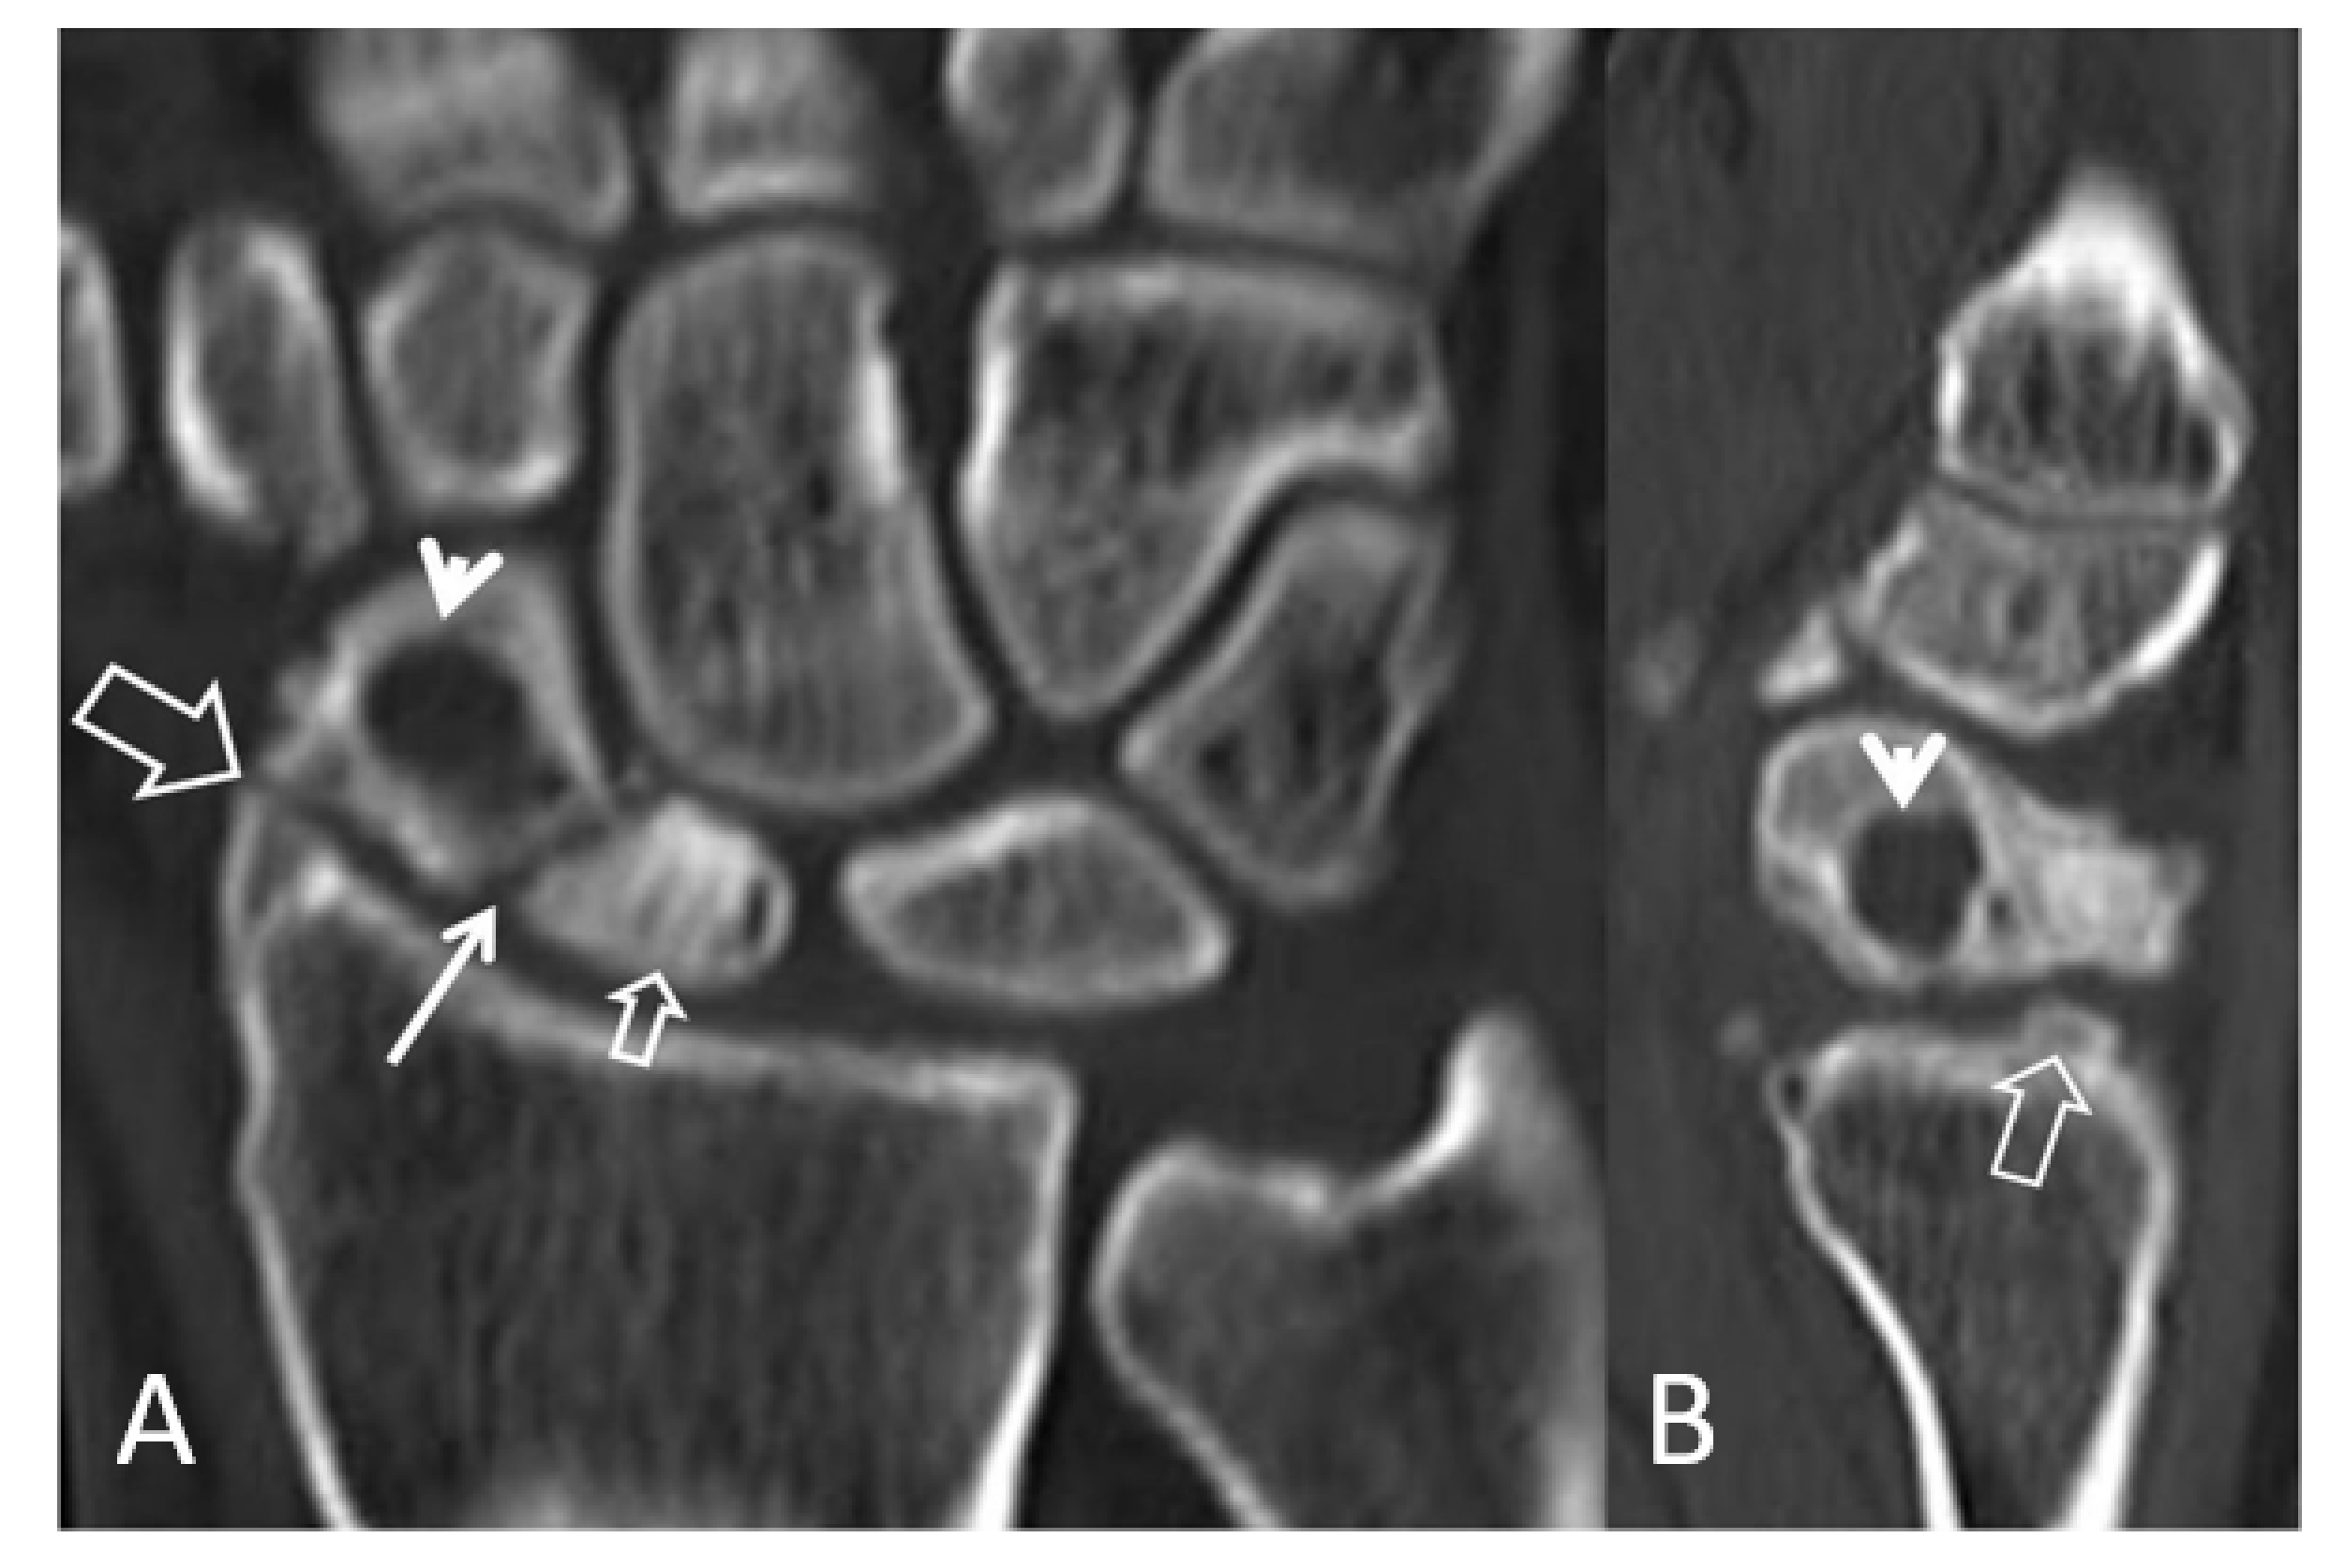

Figure 6.

Coronal (A) and sagittal (B) CT reconstructions of a 23-year-old male patient with an injury 7 years prior to current imaging. SNAC wrist is shown with radioscaphoid joint space narrowing with osteophyte formation (large open arrow left, open arrow right), secondary to proximal pole osteonecrosis (small open arrow left) and pseudarthrosis (thin arrow left). Large cyst formation is shown in the distal pole of the scaphoid (arrowheads).